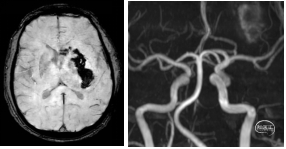

4月22日CT平扫:左侧额顶叶、放射冠区、侧脑室旁稍低密度:梗死灶?ASPECT:5分。

4月22日 CTA:左侧大脑中动脉水平段中段闭塞,远端分支稀疏。。

左侧颈总动脉正侧位:左侧大脑中动脉M1闭塞,前交通开放,双侧大脑前动脉正常,右侧大脑前动脉通过软膜支向右侧大脑中动脉供血区部分代偿。

4月23日复查CT:左侧尾状核、内囊前支梗死,左侧基底节区高密度,存在占位效应。

4月23日复查CTA:双侧大脑中动脉、大脑前动脉显影正常,左侧大脑中动脉无残余狭窄。

4月28日 复查颅脑MR平扫+FLAIR+SWI+MRA:左基底节区-半卵圆中心脑出血,破入脑室;双侧额叶、右侧顶叶、左侧颞叶多发梗死灶?双侧大脑前动脉A1段共干。